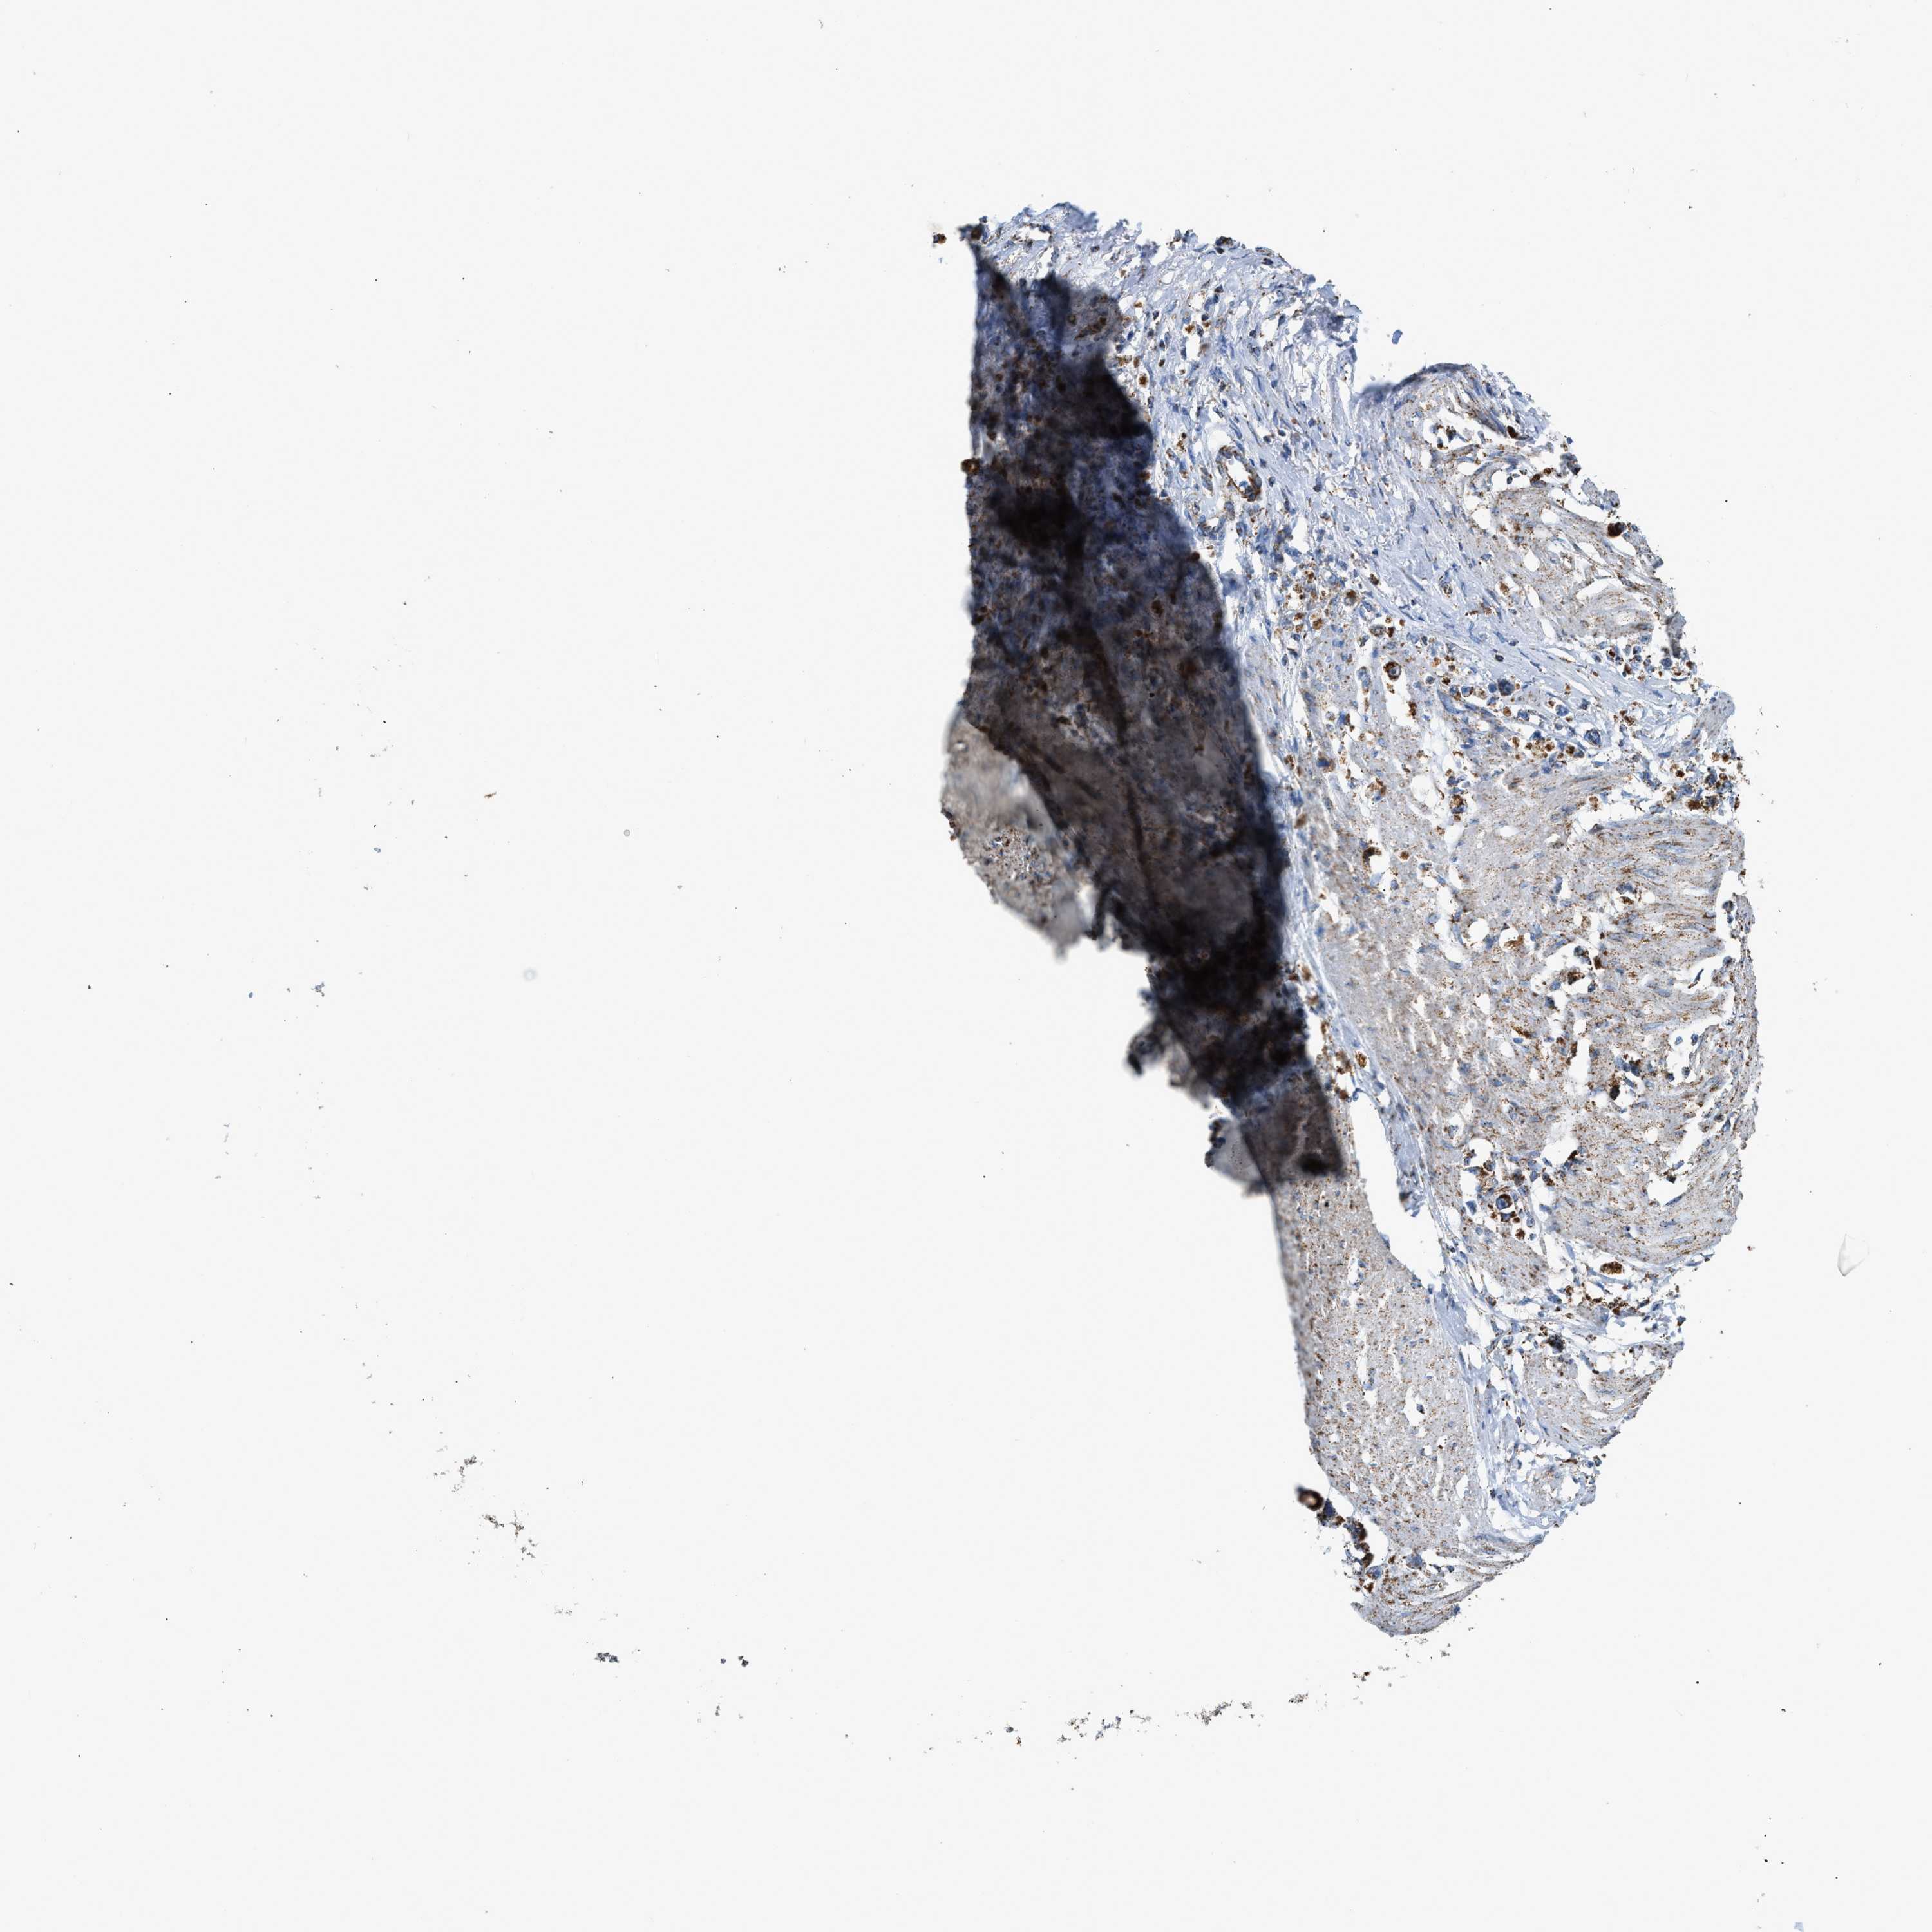

STOMACH CANCER - Protein expressioni

A mouse-over function shows sample information and annotation data. Click on an image to view it in a full screen mode. Samples can be filtered based on level of antibody staining by selecting one or several of the following categories: high, medium, low and not detected. The assay and annotation is described here.

Note that samples used for immunohistochemistry by the Human Protein Atlas do not correspond to samples in the TCGA dataset.

Antibody stainingi

Antibody staining in the annotated cell types in the current human tissue is reported as not detected, low, medium, or high, based on conventional immunohistochemistry profiling in selected tissues. This score is based on the combination of the staining intensity and fraction of stained cells.

Each image is clickable and will lead to virtual microscopy that enables deeper exploration of all samples and also displays staining intensity scores, fraction scores and subcellular localization as well as patient and tissue information for each sample.

Antibody HPA018910

Antibody HPA018921

Antibody HPA018923

Staining

High

Medium

Low

Not detected

Intensity

Strong

Moderate

Weak

Negative

Quantity

>75%

75%-25%

<25%

None

Location

Nuclear

Cytoplasmic/membranous

Cytoplasmic/membranous,nuclear

Adenocarcinoma, NOS